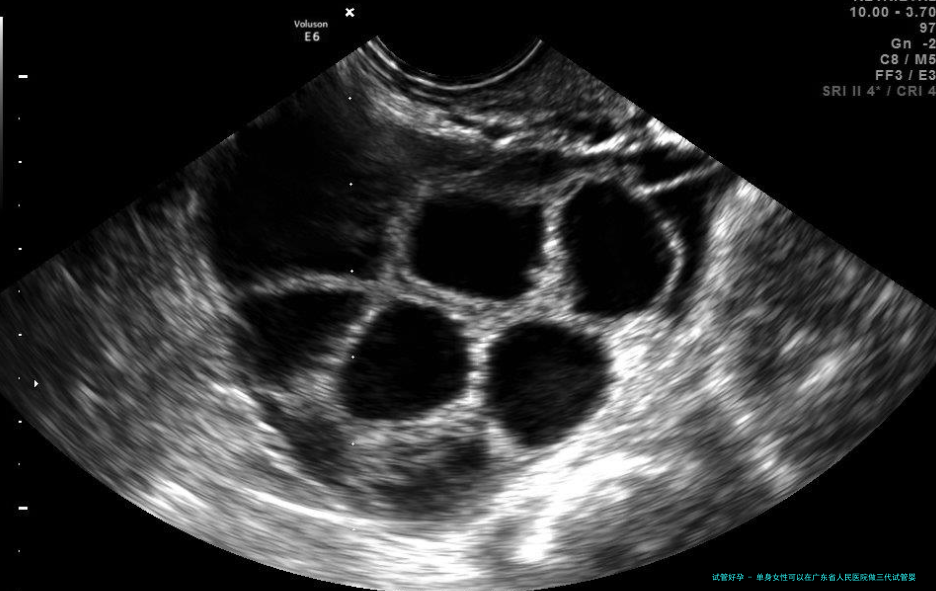

4.促排:使用药物督促女性卵巢内的多个卵泡同一时刻发育。

5.取卵:在B超引导下,经阴道穿刺取卵。